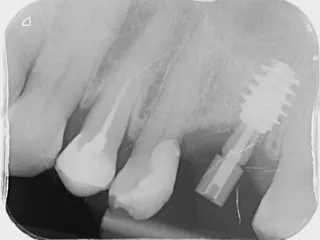

11a. 11b. Radiographs of the SSA in place and scan body for digital impressions.

11a

11b

13. Peri-apical radiograph depicting final prosthesis.

13

14a. 14b. Radiograph of 2 years follow-up.

14a

14b